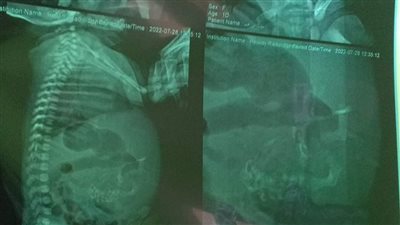

أكدت الدكتورة عبلة الألفي استشاري طب الأطفال وعضو مجلس النواب أن النسبة العالمية للأطفال المبتسرين 10% بينما في مصر تقدر بـ20% ونسبة دخول حديثي الولادة للحضانات في مصر 25% بينما النسبة العالمية 10%. وأرجعت أحد الأسباب في ارتفاع هذه النسب في مصر إلى الولادة القيصرية والتي قالت إن مصر من أعلى البلدان